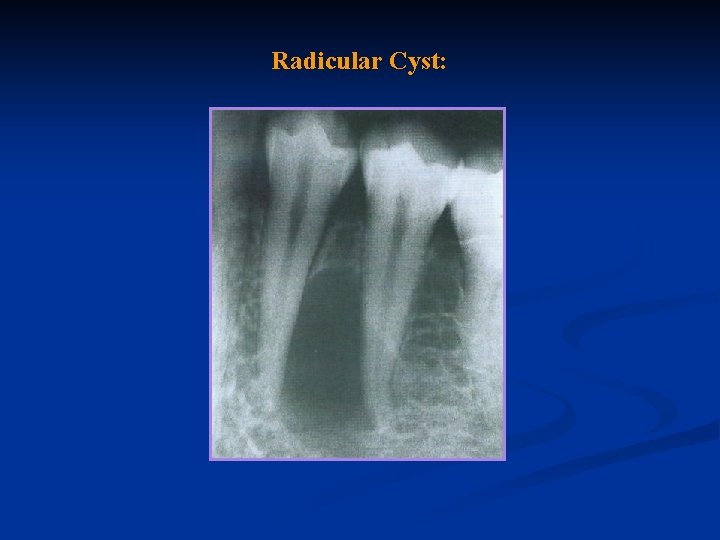

Radicular Cyst:

Definition: A cyst is a closed or sac internally lined with epithelium, the center of which is filled with fluid or semisolid material. A radicular or alveolar cyst is a slowly growing sac at the apex of a tooth that lines a pathologic cavity in the alveolar bone.

Cause: A radicular cyst presupposes physical, chemical, or bacterial injury resulting in death of the pulp, followed by stimulation of the epithelial rests of Malassez, which are normally present in the periodontal ligament: Symptoms: No symptoms are associated with the development of a cyst,

A cyst may become large enough, however, to become obvious as a swelling. The presence of the cyst may be sufficient to cause movement of the affected teeth, owing to accumulation of cystic fluid. In such cases, the root apices of the involved teeth become spread apart, so the crowns are forced out of alignment. The teeth may also become mobile. If left untreated, a cyst may continue to grow at the expense of the maxilla or the mandible.

Diagnosis: The pulp of a tooth with a radicular cyst does not react to electrical or thermal stimuli, and results of other clinical tests are negative, except the radiograph. The radiolucent area is generally round in outline, except where it approximates adjacent teeth, in which case it may be flattened and may have an oval shape. Neither the size nor the shape of the rarefied area is a definitive indication of a cyst

Differential Diagnosis: A cyst is usually larger than granuloma and may cause the roots of adjacent teeth to spread apart because of continuous pressure from accumulation of cystic fluid.

Treatment: Resolution of these areas of rarefaction occurs following root canal therapy in 80 to 98% of cases. Prognosis: The prognosis depends on the particular tooth, the extent of bone destroyed, and the accessibility for treatment